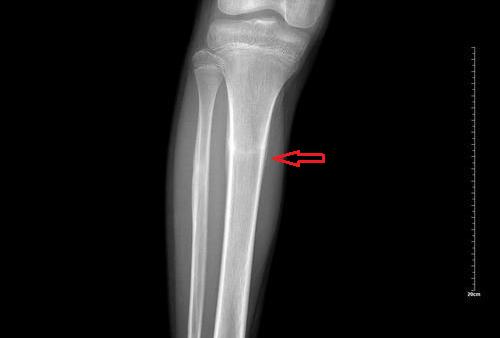

疲劳性骨折又称应力性骨折,是由于身体长期重复单一运动而造成的骨骼损伤。

当反复作用于同一位置的应力积累超过骨的疲劳极限值时,会对骨小梁造成损伤。当骨小梁被破坏时,它也会被处理。当损伤速度超过修复速度时,就会引起疲劳性骨折。

X线对疲劳性骨折的检出率约为50%,CT诊断率约为80%,MRI(磁共振)诊断率接近100%。所以,磁共振是诊断疲劳性骨折的最佳方法。